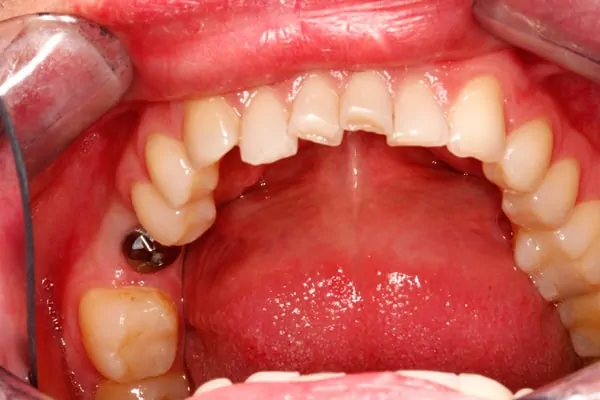

At Kavita Patel, DDS in Colonia, NJ, we know that seeing is believing! Our Smile Gallery is filled with real patient transformations, showcasing dental implants before and after, Invisalign before and after, and crowns before and after results. Thinking about a smile makeover? A smile makeover is more than just aesthetics—it’s about confidence, comfort, and health. See how our patients have achieved stunning transformations with straighter, brighter, and complete smiles. Explore our before and after images and imagine what’s possible for you. A confident, healthier smile starts with a single step—schedule your consultation today! Book a consultation today!